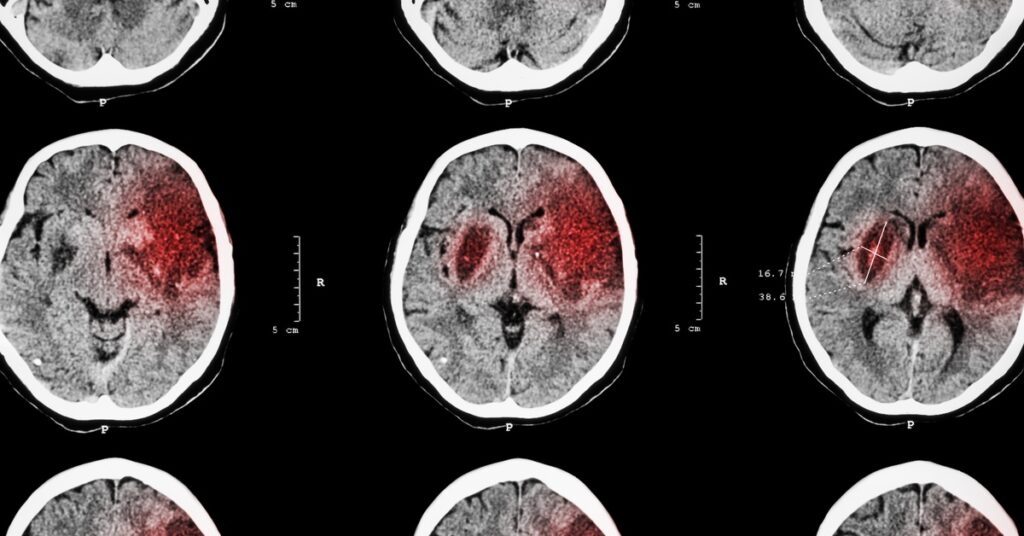

Tissue plasminogen activator, also known as tPA, is a medication commonly given to people who have suffered strokes. What are the risks of this approach?